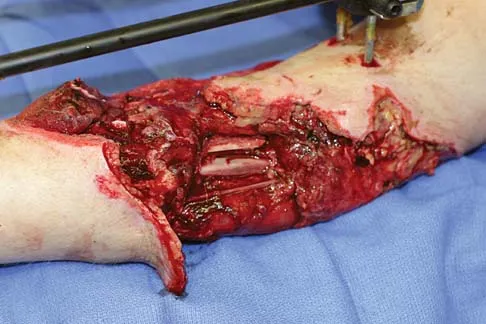

A 13-year-old girl was riding on an all-terrain vehicle when the driver struck a tree. She sustained the injury shown in Figures 45a through 45d. This injury is best described as what type of acetabular fracture pattern?

Explanation